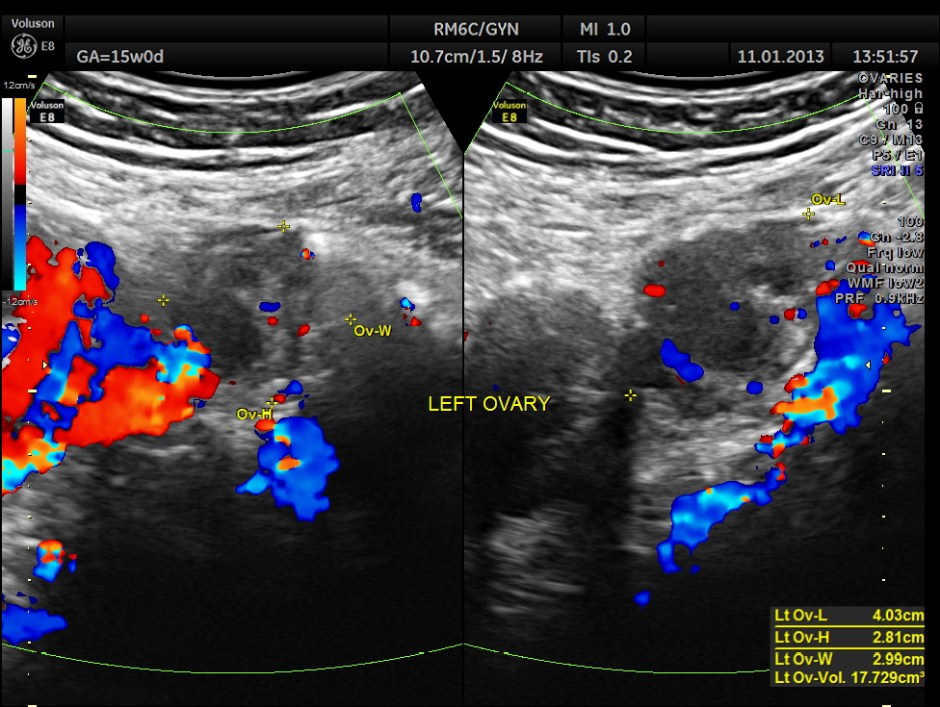

Left ovary was also seen to be normal.